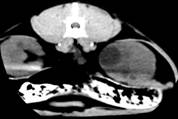

Даний факт знаходить підтримку у роботах

сучасних дослідників гуманної медицини в цій галузі. Досліджуючи цю тварину

через 14 днів, ми відзначили зниження інтенсивності сигналу вищевказаного

кістозного утворення (рис.).

Поясненням цього може бути поступовий розпад гемоглобіну, що зменшує

інтенсивність сигналу. Це припущення також висувається у гуманній медицині. В

той же час, інтенсивність деяких кістозних утворень залишалась постійно

високою, що може вказувати на інфікування вмісту кісти та зумовлене наявністю

великої кількості білка у кістозній рідині. Така тенденція знаходить

відображення у деяких публікаціях.

Рис.7. КТ

нирок кота. Полікистоз в стадії компенсації: а-неускладнена кіста; б -

геморагічна кіста

Рис. 8. КТ

кота. Полікистоз нирок у стадії субкомпенсації. Деформація

миски

правої

нирки.

Зменшення

інтенсивності

сигналу

геморагічної

кісти

(а)